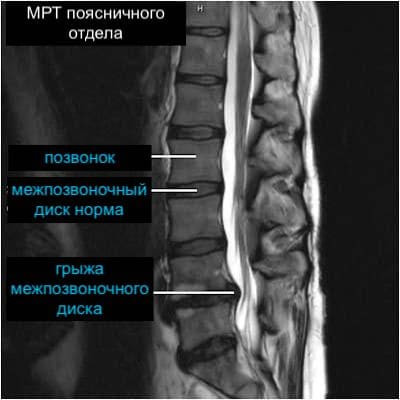

Фото из интернета для наглядности. Выглядит вовсе не страшно

А если все-таки сделать МРТ?

Вы сделаете снимок, вам, скорее всего, скажут: «протрузия, остеохондроз или спондилёз…», и это будет звучать, конечно, тревожно. Но на самом деле эти “диагнозы” есть у половины человечества, причем даже и у тех, у кого ничего не болит.